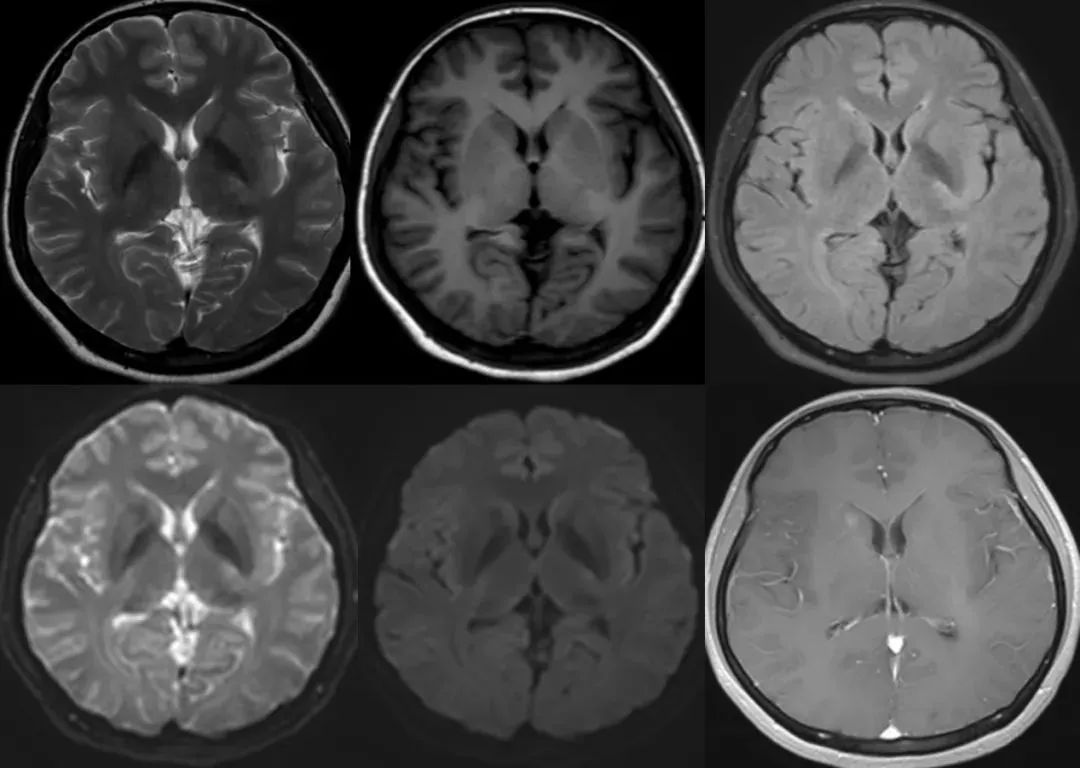

右侧放射冠相对较大的毛细血管扩张症,T2WI 和 FLAIR 呈高信号,SWI 呈低信号,增强呈片状稍淡样强化,可见引流静脉至室管膜下